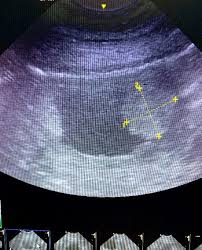

Bladder Cancer In Dogs Symptoms Causes And Treatment Dogzhealth Com from www.dogzhealth.com Symptoms of bladder cancer are identical to those of cystitis. Other signs may include lethargy, exercise intolerance, reduced appetite, weight loss, and pain (especially along the back or abdomen). Also, spinal cord injuries can render a pet unable to urinate. The veterinarian will palpate your dog's bladder and urethra and perform a rectal examination, which may reveal stones in the bladder or urinary tract or an enlarged prostate in male dogs. Symptoms of bladder cancer in dogs dogs that are suffering from bladder cancer will be in pain and will exhibit signs of having difficulty urinating. Pets may strain to urinate or defecate, and the stools may become flattened or ribbonlike. Invasive transitional cell carcinoma (tcc) is the most common form of canine urinary bladder cancer affecting tens of thousands of dogs worldwide each year, and the prevalence appears to be on the rise. Recent studies have revealed the presence of lesions in both the bladder and the urethra.

The pain may be significant in pets that have evidence of metastasis (spread) to the bones of the lower back and pelvis. Additionally, disease of the prostate gland can cause urinary obstruction in males only, as females do not have a prostate gland. The most common symptom of bladder infections in dogs is the frequent urge to urinate, even when there's little or no urine present. These include small, frequent urination, painful urination, bloody urine and incontinence. Urinary bladder cancer in dogs is a challenging disease to diagnose, stage, and treat.

If your dog collapses, get to the vet immediately. The signs and symptoms of bladder cancer can vary based on the size and location of the tumor as well as the stage of the disease. Symptoms will often improve initially with administration of antibiotics (as bladder infection is a common concurrent disease) but then recur a short time later. Overview of canine bladder cancer: Urinary bladder cancer in dogs is a challenging disease to diagnose, stage, and treat.